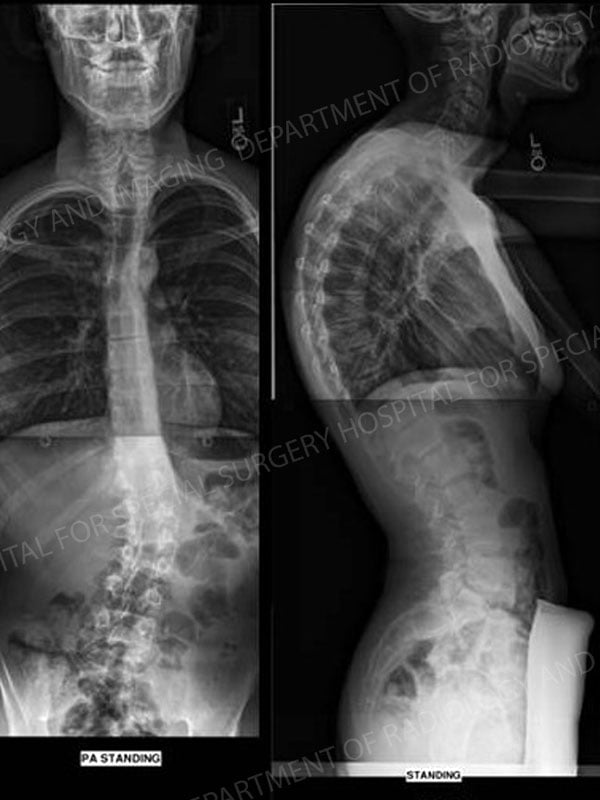

Figures 1 & 2:

16-year-old male who presented with Scheuermann kyphosis

Figure 1. Pre-Operative x-ray images demonstrating a 80° thoracic kyphosis and a 22° thoraco-lumbar scoliosis.